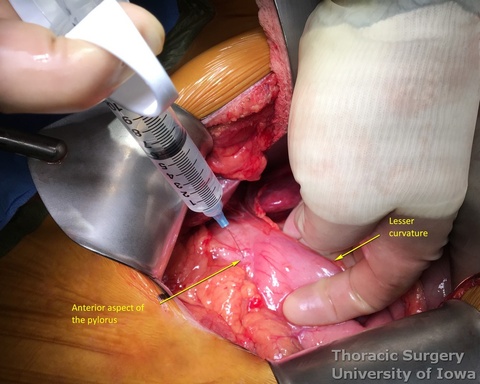

- Injection of 200 units of Botox diluted in 8 mL of normal saline is performed anteriorly and posteriorly into the pylorus (divided in 2 mL portions in four quadrants) to improve gastric emptying postoperatively. No pyloromyotomy is needed then.

- Alternatively, pyloromyotomy can be performed using an electric cautery to divide the pyloric muscle.